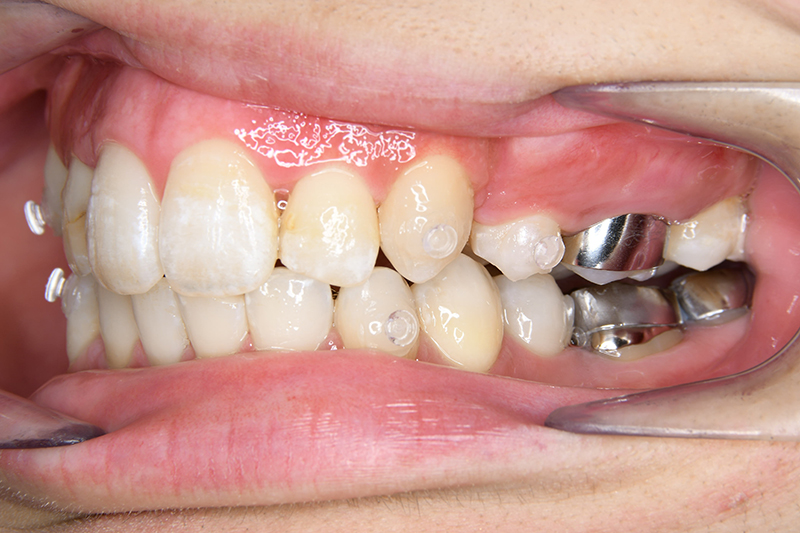

初診時

FP・IOP

口腔内所見 over jet 11.5mm、over bite 5.5mm、右側臼歯関係Full ClassⅡ級、左側end onⅡ級、上顎顎歯列はテーパー型であり、上顎中切歯は押し出されるように大きく唇側傾斜していた。下顎前歯部は叢生を呈しており、左下5は歯冠長が短く半埋伏していた。